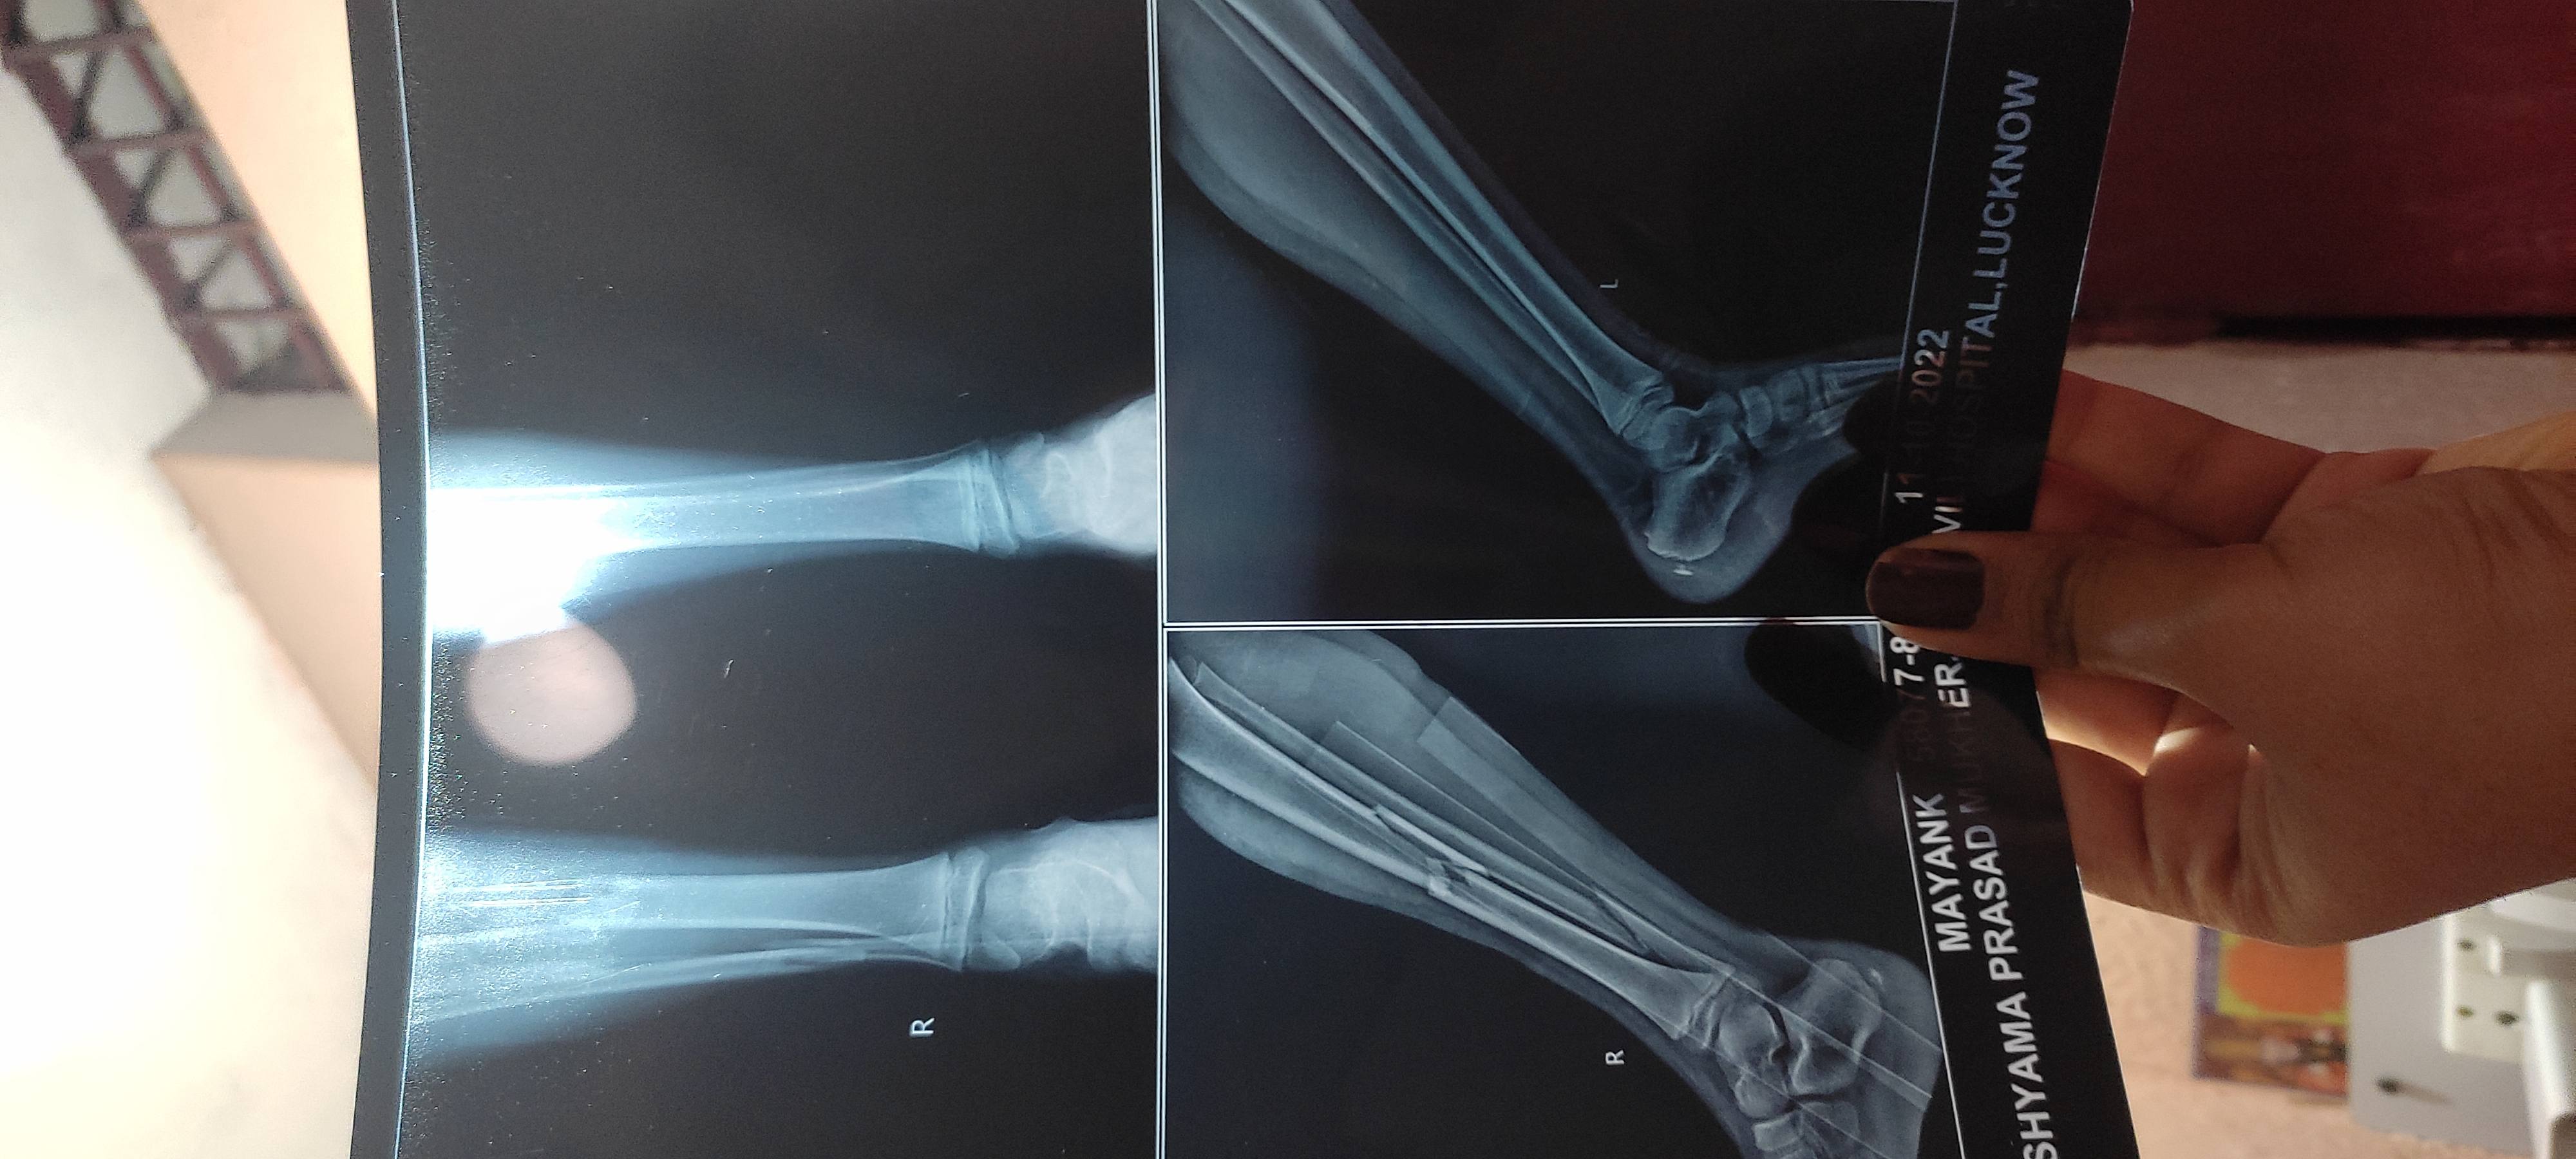

Isme operation karwana sahee rahega